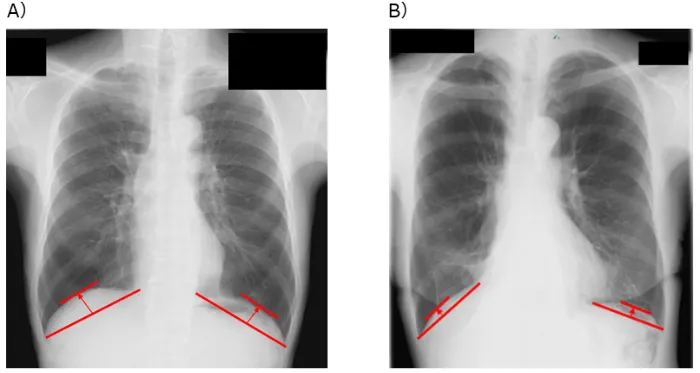

本研究は、近畿大学病院で肺葉切除術を受けた、閉塞性換気障害を伴う肺がん患者302人を対象に課題を設定しました。術前1カ月以内に撮影された胸部X線画像を使用し、横隔膜ドーム高という指標を測定しました。このデータと、術後の生存率や合併症発生の状況との関連性を解析しました。

研究の結果、術前の横隔膜ドーム高は、術後3年の生存率に有意に影響を及ぼすことが確認されました。具体的には、横隔膜が低い位置にある患者のグループは、術後において生存率が低く、呼吸器疾患による死亡率も高いことが判明しました。この結果から、胸部X線による簡単かつ負担の少ない評価が可能である横隔膜ドーム高が、肺がん患者の治療における重要な指標となり得ることが示されました。